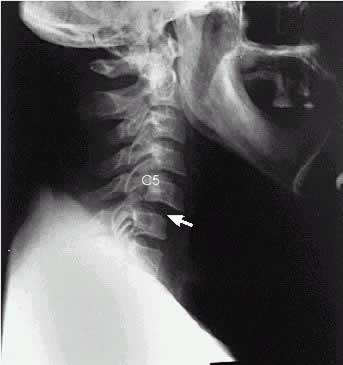

Cervical spine with anterior subluxation

subluxation / vertebral subluxation

Subluxation (sub·lux·a·tion) (sub"l?k-sa´sh?n)

[ sub- + luxation ] 1. an incomplete

or partial dislocation .

See accompanying illustration. 2. in chiropractic,

any mechanical impediment to nerve function; originally,

a vertebral displacement believed to impair nerve function.